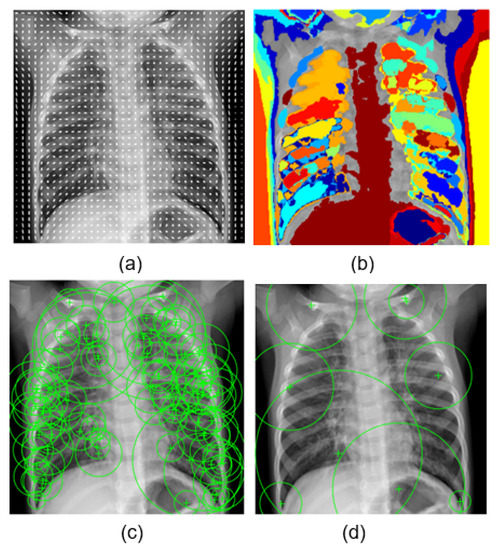

- HOG: Histogram of gradient feature, a grid of equally spaced region plots, is used to show HOG features [45]. The grid dimensions are determined by the image size as well as the cell size. The distribution of gradient orientations within an HOG cell is displayed on each region plot. The region used was a block of cell. The learning was performed by using the strongest 17,693 features from each of the image classes.

- MSER: Maximally stable extremal region is a feature object detector [46]. The MSER object examines changes in region area between various intensity thresholds. Threshold values are used to maintain the circular regions, where circular regions have low eccentricity. The circular region range was [30 14000], and the value of the threshold was 2. Decreasing the value of the threshold will return more regions. The learning was carried out using the 28,550 strongest features.

- SURF: Speeded up robust feature is a patented local feature detector and descriptor [47]. SURF finds landmarks and describes them using a vector that is somewhat resistant to distortion, rotation, and scaling. For this experiment, we used these parameters: number of octaves = 5, number of intervals = 4, and threshold = 0.0004. The most powerful 22,895 features from each of the image classes were used to perform the learning.

- BRISK: Binary robust invariant scalable keypoint is a scale- and rotation-invariant feature point detection and description tool [48]. We used the following parameters for this experiment: number of corners = 0.1, number of octaves = 4, and intensity difference = 0.2. The 6953 most effective features from each class were used to carry out the learning.